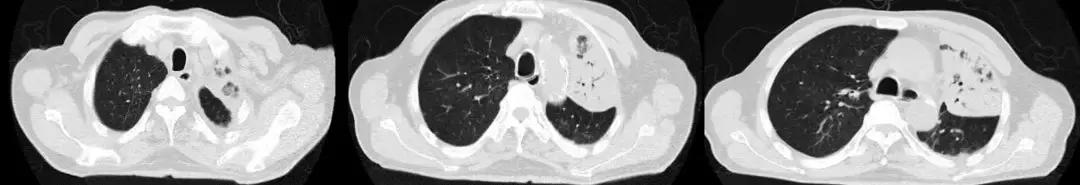

您能根据影像判断患者是病毒感染吗?但是在广谱抗生素抗感染治疗无效的ARDS患者,一定警惕病毒感染。

男,67岁,急性病程;发病前有旅游病史;主诉:发热、干咳伴呼吸困难2天,加重1天;查体:体温38.3℃,心率96次/分, 呼吸35次/分,血压98/63mmHg,SpO2 88%(FiO20.37),急性病容,呼吸急促,左肺呼吸音粗,右下肺呼吸音减弱,双下肺可闻及湿啰音;肺部CT示双下肺渗出、实变影,动脉血气分析提示I型呼吸衰竭。

2017-9-26

2017-9-29